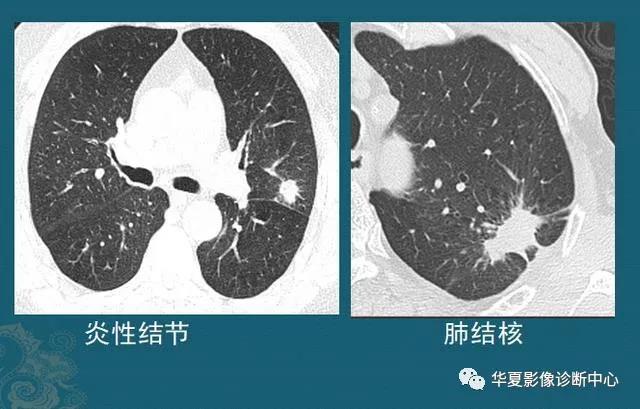

下图左边是一个炎症性结节,右图是结核球,都是形态不规则,边缘有毛刺,伴有胸膜牵拉:

这种结节有时单纯从CT片的形态分析,跟肺癌鉴别困难,需要抗炎治疗后复查,或者增强CT看结节的强化特点,炎症结节常常明显均匀强化,结核球一般不强化或者环形包膜样强化(肺结核会破坏内部组织包括血管,引起广泛坏死),肺癌多为轻中度不均匀强化(肿瘤血管少而乱)。

还有些无法确诊的,需要多学科会诊,借助PET-CT或者穿刺,或者手术后病理等手段。